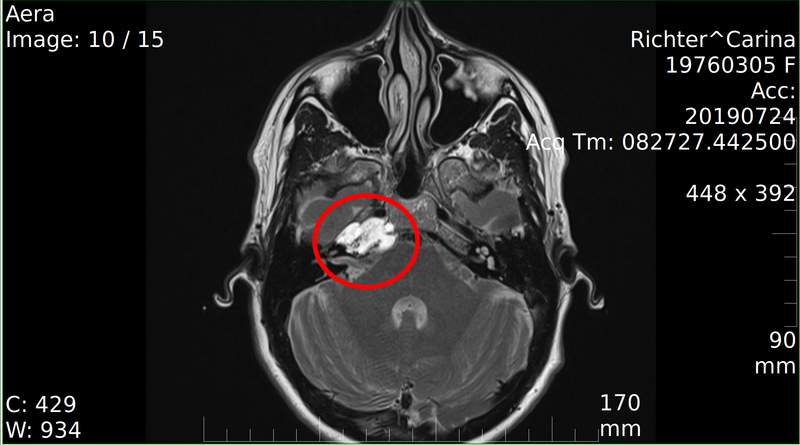

Carina Richter liebt das Leben – und doch hat es ihr eine außergewöhnliche Herausforderung gestellt. Als Mutter von vier Kindern, ehemalige Krankenschwester und Mensch mit Herz und Humor erhielt sie im September 2019 eine Diagnose, die alles veränderte: ein seltener, aggressiver Knochentumor an der Schädelbasis, mitten am Hirnstamm. Der Befund war ein Zufallsfund im Rahmen einer Studie. „Das Erste, was ich dachte, war: Ich sterbe“, erinnert sie sich. Angst, Panik und Ungewissheit prägten die ersten Tage.

Doch Carina Richter ist eine Kämpferin. Sie gibt ihrem Tumor den Namen „die Meise“ und vereinbart humorvoll: Die Meise darf bleiben, aber sie soll sich benehmen. Mit dieser Mischung aus Pragmatismus und Humor geht sie ihren Weg – unterstützt von Prof. Dr. med. Christian Ewelt, Chefarzt der Neurochirurgie an der St. Barbara-Klinik Hamm-Heessen. Zwei riskante Operationen stehen an, deren Folgen Schluckstörungen, Gleichgewichtsstörungen und Lähmungen sein können. Dennoch bleibt sie positiv, kämpft sich ins Leben zurück und lernt, mit den Einschränkungen umzugehen.

Medizinischer Weg und Therapie

Nach der Diagnose eines Chondrosarkoms am Hirnstamm begann ein intensiver medizinischer Weg. Bereits wenige Tage nach dem Befund folgten MRT- und CT-Untersuchungen. Im Oktober 2019 erfolgte die erste Operation, gefolgt von einer zweiten, komplexen Neurochirurgie im selben Jahr – beide unter Leitung von Prof. Dr. Ewelt. Die Eingriffe waren hochriskant, da der Tumor in unmittelbarer Nähe zu lebenswichtigen Hirnstrukturen lag. Vorübergehende neurologische Ausfälle wie Schluckstörungen, Gleichgewichtsstörungen und Lähmungen traten auf.

Im Anschluss erhielt Carina Richter eine siebenwöchige Protonentherapie am Heidelberger Ionenstrahl-Therapiezentrum (HIT), die besonders das umliegende gesunde Gewebe schont. Seitdem begleiten regelmäßige Nachsorgeuntersuchungen den weiteren Verlauf.